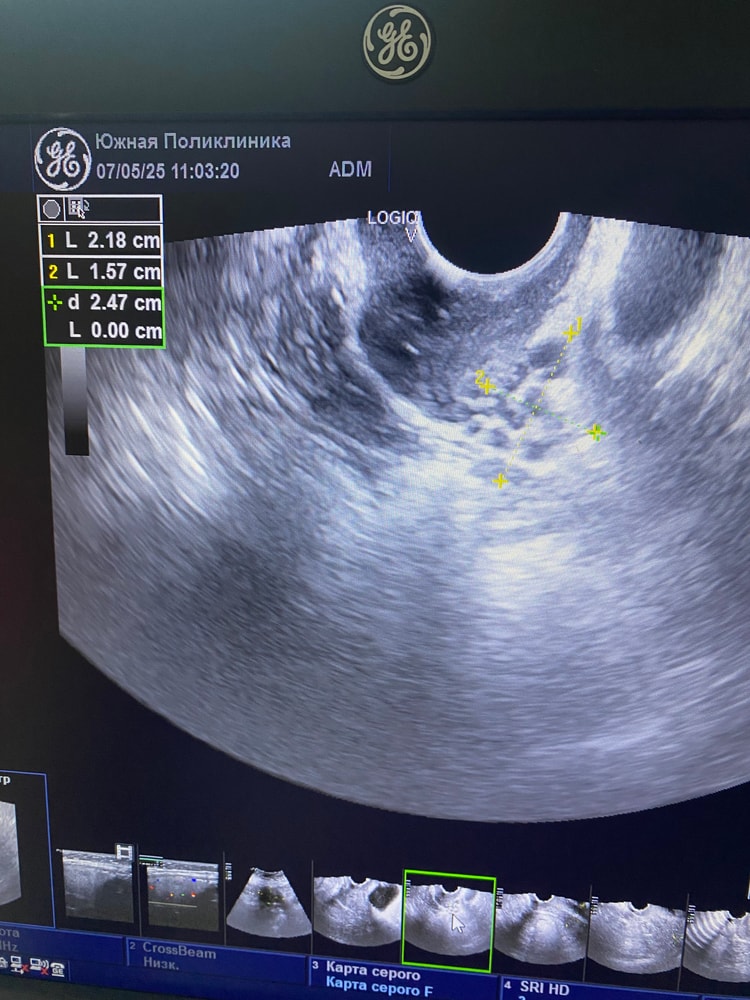

Ну по фото его нет, зато много мелких

Судя по снимку, его и правда нет, его сложно не заметить. Вообще до 2 раз в год цикл может быть без овуляции, если больше, то нужно идти к эндокринологу, проверять гормоны

Даша, конечно, доминантный фоликул только слепой может не заметить. Как уже ниже писали, по узи картине он выглядит как чёрная большая дыра

Вот фото для примера, сверху мелкие фоликулы как у вас и один большой доминантный ниже

Все возможно, конечно, но ДФ очень хорошо видно, он огромный как черная дыра😅 я первый раз увидела-обалдела. Скорее всего цикл будет без О. На фото у вас и правда нет ДФ.